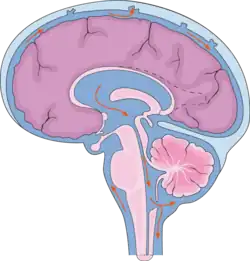

Ликвор циркулирует в субарахноидальном пространстве вокруг головного и спинного мозгов, а также в желудочках головного мозга

Спинномозгова́я жи́дкость, или ли́квор (лат. liquor cerebrospinalis[1]) — жидкость, постоянно циркулирующая в желудочках головного мозга, ликворопроводящих путях, субарахноидальном (подпаутинном) пространстве головного и спинного мозга[2].

Циркуляция

Ликвор образуется в мозге: в эпендимальных клетках сосудистого сплетения (50—70 %), вокруг кровеносных сосудов и вдоль желудочковой стенки. Далее цереброспинальная жидкость циркулирует от боковых желудочков в отверстие Монро (межжелудочковое отверстие), затем — вдоль третьего желудочка, проходит через Сильвиев водопровод. Затем проходит в четвёртый желудочек, через отверстия Мажанди и Лушки выходит в субарахноидальное пространство головного и спинного мозга. Ликвор реабсорбируется в кровь венозных синусов и через грануляции паутинной оболочки.